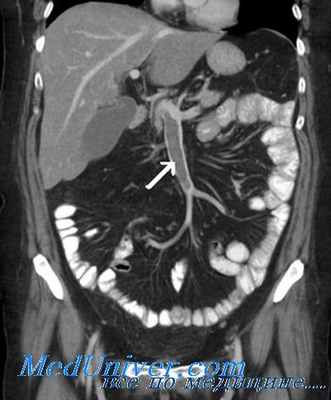

Ангиография при мезентриальном тромбозе

Мультиспиральная компьютерная томография аорты и ее ветвей позволяет точно оценить состоянии брыжеечных сосудов и помочь правильной постановке диагноза. Признаками острой мезентериальной непроходимости является отсутствие контрастирования брыжеечных артерий со слабым развитием коллатеральных сетей кровообращения. При соответствующих жалобах и клинической картине компьютерная томография позволяет поставить точный диагноз в большинстве случаев мезентериального тромбоза. Требуется внутривенное введение контраста и детальный анализ полученных изображений.

![Ангиография позволяет поставить точный диагноз и выполнить вмешательство по восстановлению кровообращения]()